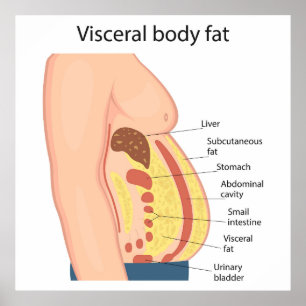

Poster Gordura do corpo visceral

Preço89,90 €